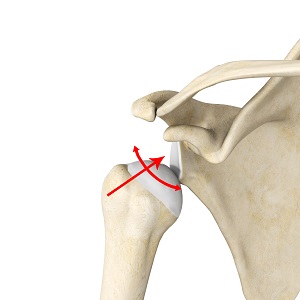

The shoulder consists of a ball and socket joint where the rounded end of the humerus (upper arm bone) fits into a socket (glenoid cavity) formed by the shoulder blade. The joint is stabilized by the surrounding capsule, ligaments, and tendons of the rotator cuff muscles. Shoulder instability results when the humerus is not held firmly within the socket and moves away from the glenoid cavity. This may be due to a defect or injury to the supporting structures and can result in a partial dislocation (subluxation) or total dislocation of the shoulder joint.

Instability may be described by the direction in which the humerus is subluxated or dislocated from the glenoid. When it occurs in several directions it is referred to as multidirectional instability.

Arthroscopy involves the insertion of a thin device with a camera to view the shoulder joint on a monitor and perform the necessary surgical procedure. Open surgery involves a larger incision and the procedure is performed under direct visualization. The most common surgery performed for multidirectional instability is a capsular shift where the capsule and ligaments enclosing the shoulder joint are tightened.